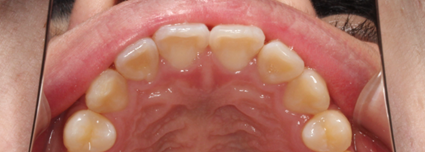

部分矯正とは全部の歯ではなく、前歯など気になる歯の部分を矯正する治療方法です。

そのため「人から見られやすい前歯だけを直したい」「すきっ歯だけを直したい」と希望する方に適している治療法でもあります。